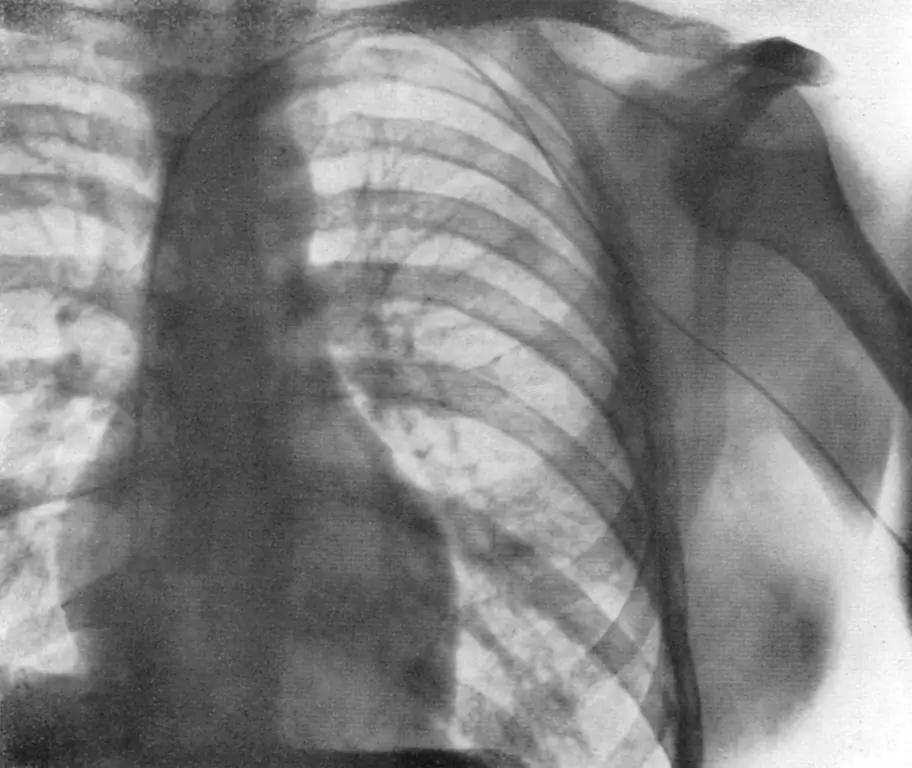

«Она была зла», - вспоминает он журналиста New York Times Лоуренса К. Альтмана. «Я попросил ее сохранять спокойствие, обвязать мне руку платком и вызвать рентгенолога. Вместе мы спустились в его отделение, которое находилось в подвале». Там Форссманн стоит за флюороскопом, рентгеновским аппаратом, который в то время использовался для таких обследований. Он просит Дитцена, который находится с другой стороны, поднять зеркало, чтобы он мог сам увидеть, где именно находится катетер.

Недостаточно далеко, на его вкус. Поэтому он толкает его дальше и следит в зеркале за тем, как катетер приближается к его сердцу. А затем следует следующая драматическая кульминация. Потому что Форссманн и Дитцен не заметили, как техник тихо вышел из комнаты. Он возвращается, но не один, а с главой отдела Питером Ромейсом. Как только он оправится от увиденного, его предохранитель сгорит.

«Он пытался вытащить катетер из моей руки», - позже сообщает Форссманн. «Я пытался остановить его, крича: «Нет, нет! Я должен добраться до сердца!» Я сильно ударил его ногой по голени, а когда он корчился от боли, толкнул катетер дальше, пока не смог увидеть в зеркало "Фото! Сделайте фото! Сейчас же!" - кричал я технику, потому что мне нужно было иметь осязаемое доказательство того, что эксперимент сработал."